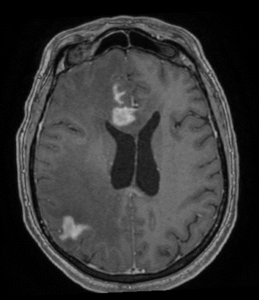

IRM cerebral cu substanță de contrast – metoda de elecție. Limfoamele sunt leziuni cu hipersemnal T2-FLAIR și hiposemnal T1, imprecis delimitate, cu contrast intens, adesea periventriculare si cu aspect caracteristic de difuzie (ADC). Poate mima glioblastomul sau metastazele cerebrale.

Limfoamele cerebrale apar frecvent în emisferele cerebrale, ganglionii bazali, corpul calos, talamus și periventricular.